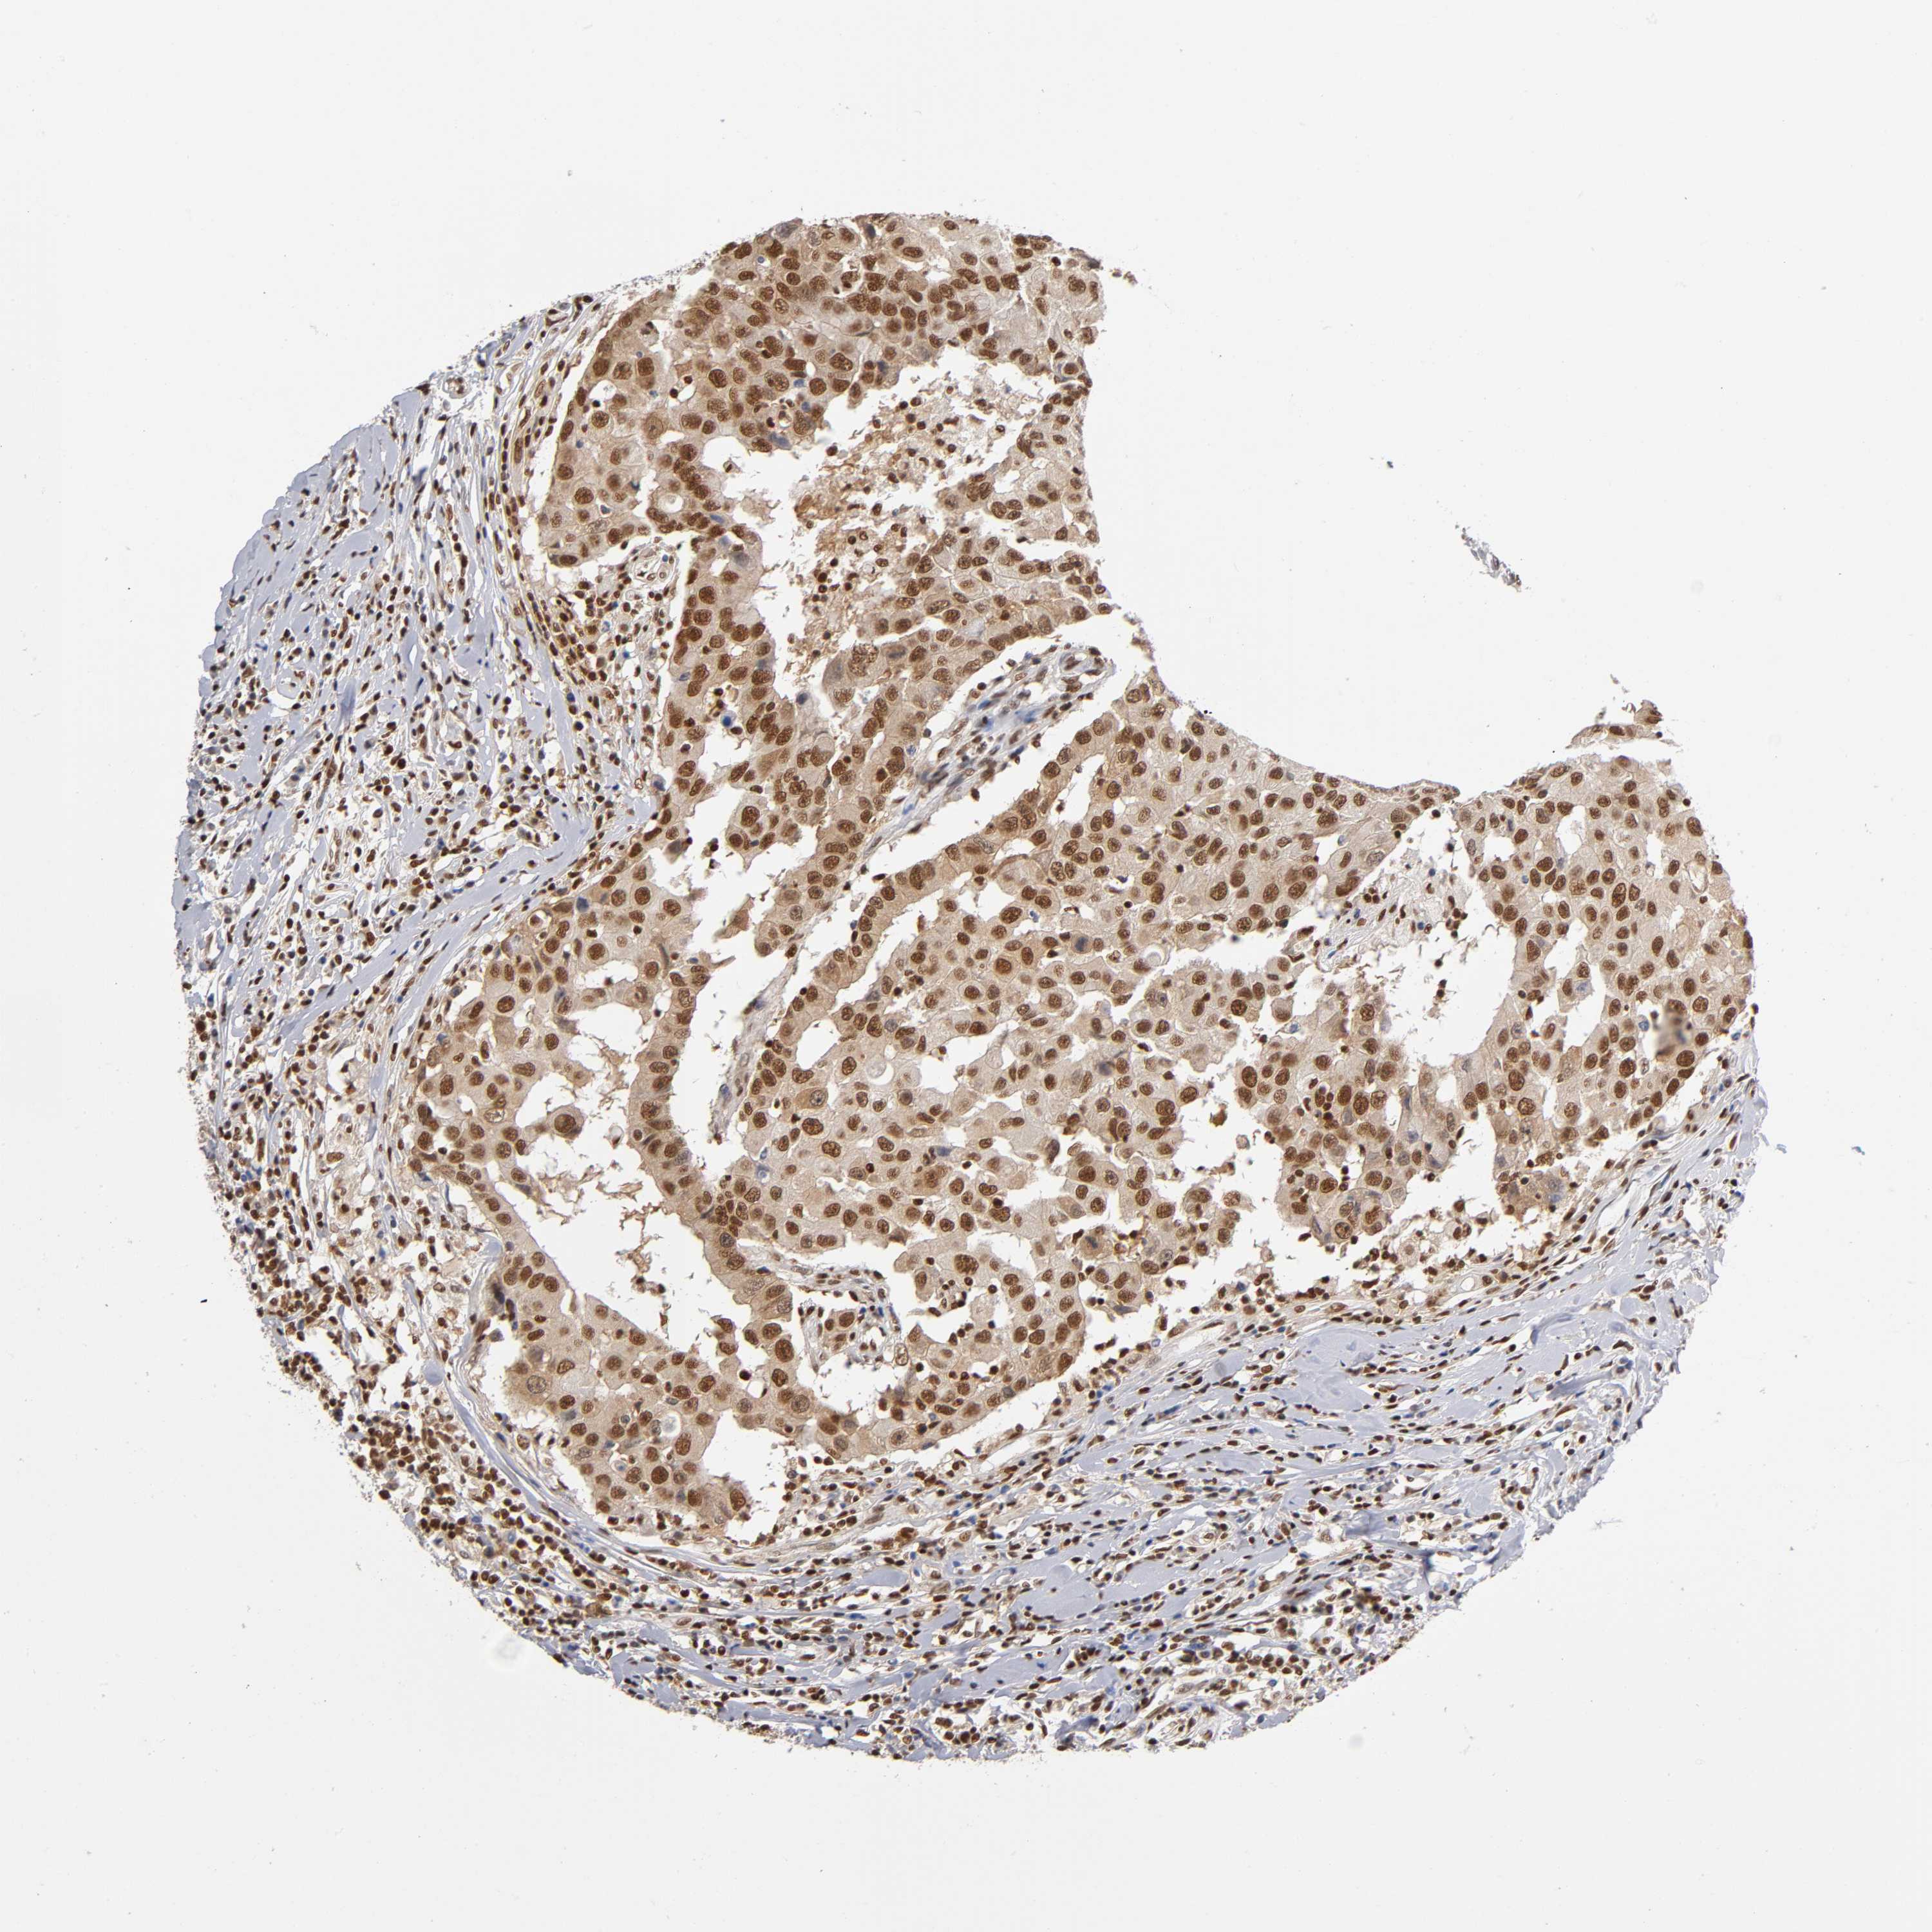

CANCER BREAST CANCER Show tissue menu

BRCA TCGA BRCA VALIDATION PROTEIN EXPRESSION